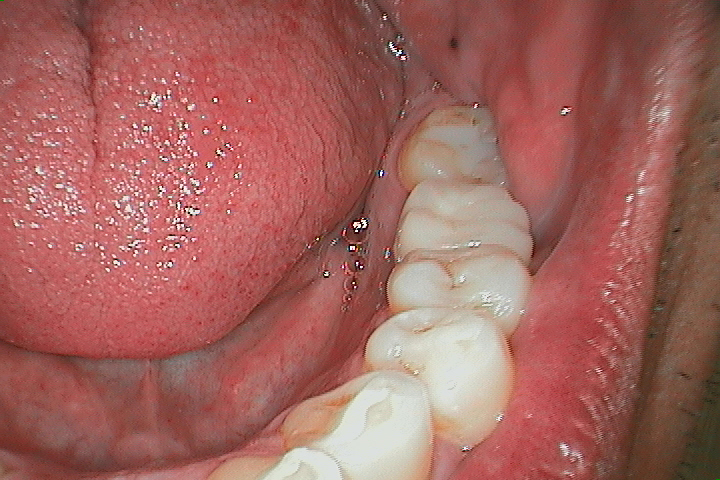

欠けている歯のためのブリッジ治療

前

![橋の前に隙間のある歯]()

後

![ブリッジ配置後の歯]()

後

![ブリッジ配置後の歯]()